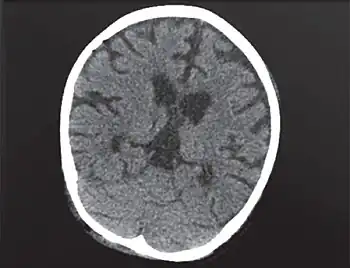

| Individual with PNP deficiency -cerebral and cerebellar atrophy, deepening of cerebral sulci | |